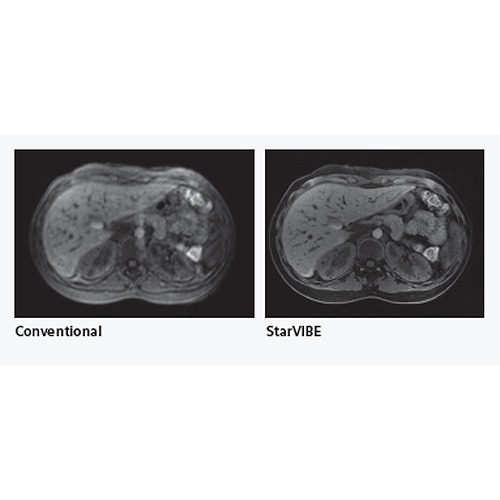

●FREEZEitは、肝臓の3D造影検査を様々な状況下で高品質な撮像画像を得るための新しいコンセプト機能です。「StarVIBE」 と「 TWIST-VIBE」 の新しい撮像シーケンスが含まれています。